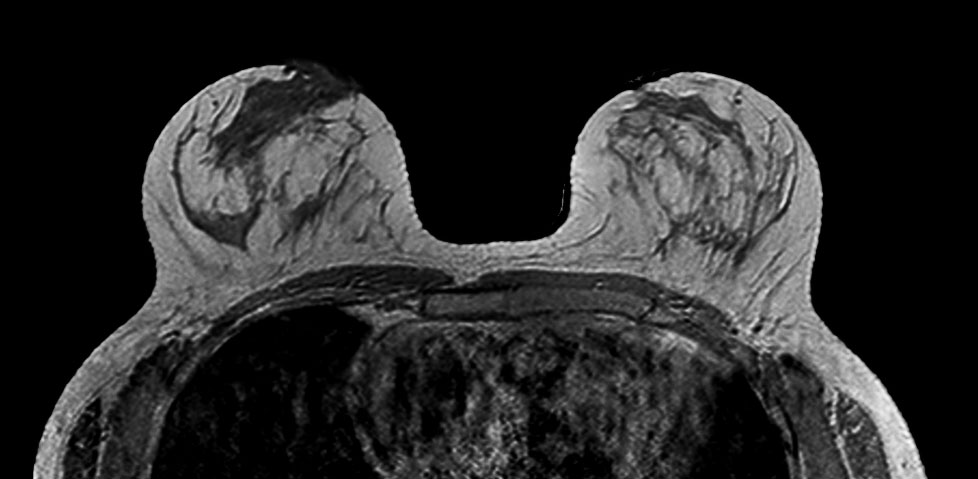

Breast imaging using SmartExam

Used Solution